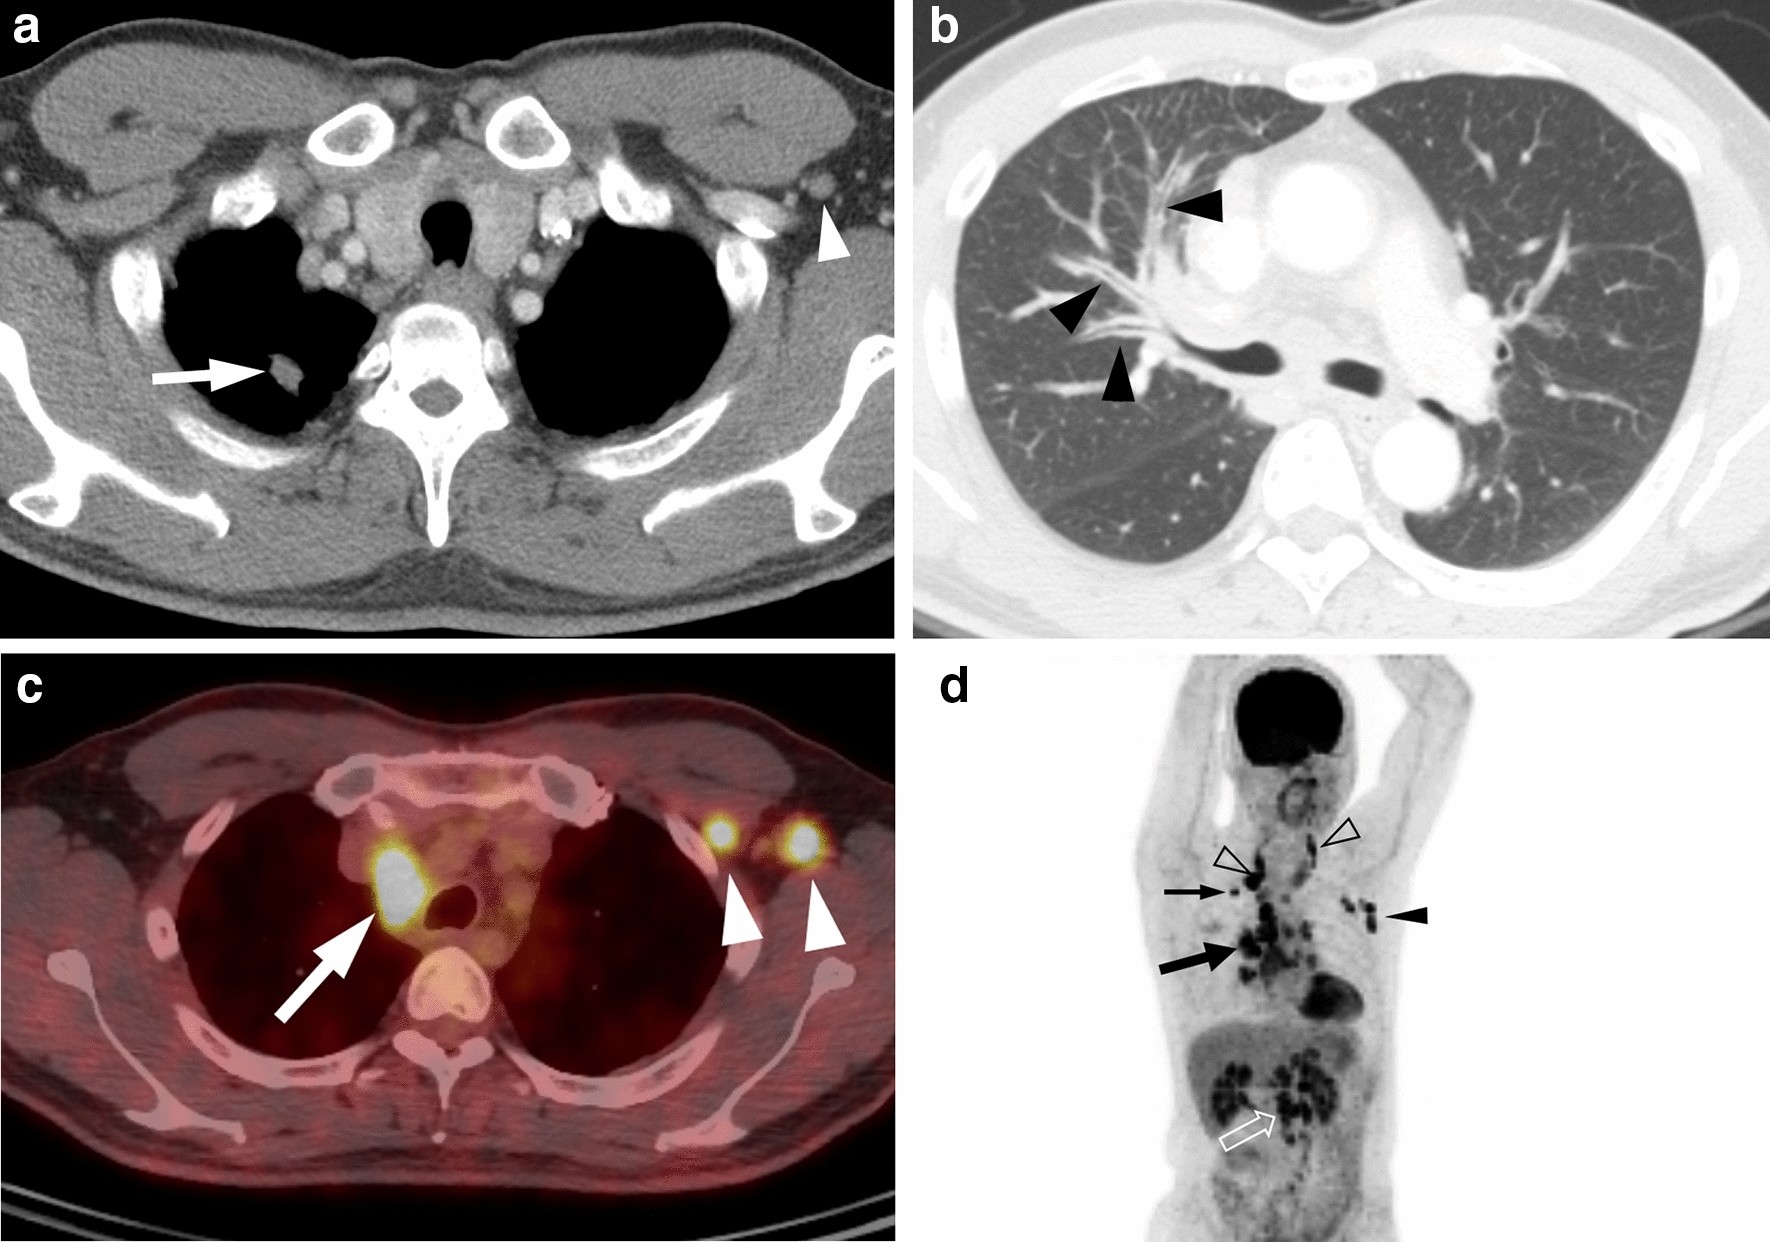

Figure 1

A 44-year-old man with ROS1-rearranged lung adenocarcinoma with extensive lymph node metastases. (a) Transverse mediastinal CT image demonstrates a small solid nodule (arrow) in the right upper lobe, which is presumed to be a primary tumor. Left axillary lymph node enlargement (arrowhead) is also noted. (b) Transverse lung window CT image shows diffuse bronchial wall thickening (arrowheads), which represents lymphangitic carcinomatosis. (c) Fused PET/CT image demonstrates fluorodeoxyglucose (FDG)-avid right paratracheal (arrow) and left axillary (arrowheads) lymph nodes. (d) Maximum intensity projection image of PET shows intense FDG uptake in the primary tumor (thin arrow), cervical (open arrowheads), mediastinal (thick arrow), left axillary (arrowhead), and intraabdominal (open arrow) lymph node metastases.